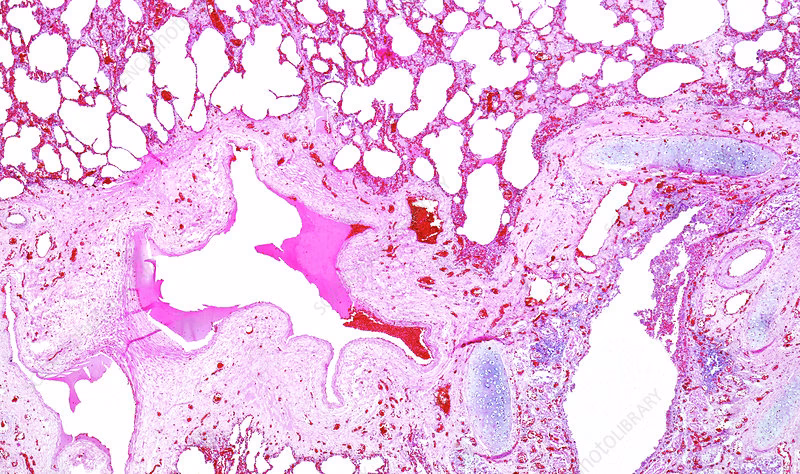

Når en vævsprøve (biopsi) fra en persons bronkier undersøges under et mikroskop, afsløres en række karakteristiske forandringer, der tilsammen tegner et billede af kronisk bronkitis. Disse forandringer er kroppens fejlslagne forsøg på at beskytte og reparere sig selv mod konstant irritation.

Et af de mest fremtrædende træk er en markant forøgelse i antallet og størrelsen af bægerceller i luftvejsepitelet – en tilstand kendt som bægercellehyperplasi. Bægerceller er specialiserede celler, hvis primære funktion er at producere mucus (slim). I en sund lunge hjælper et tyndt lag slim med at fange støv, pollen og andre partikler, som derefter transporteres ud af lungerne af små fimrehår (cilier). Ved kronisk bronkitis går denne produktion i overgear. Den konstante irritation stimulerer bægercellerne til at formere sig og producere enorme mængder tykt, sejt slim. Dette fører til:

- Luminal ophobning af slim: Luftvejens indre rum (lumen) bliver fyldt eller blokeret af slim.

- Nedsat ciliefunktion: Det tykke slim lammer fimrehårene, så de ikke effektivt kan fjerne slimen.

- Produktiv hoste: Kroppens eneste tilbageværende metode til at fjerne slimen er ved at hoste den op.

- Øget infektionsrisiko: Den stillestående slim er en ideel grobund for bakterier, hvilket fører til hyppige lungeinfektioner.

3. Infiltration af Inflammatoriske Celler

Kronisk bronkitis er, som navnet antyder, en inflammatorisk tilstand. Histologiske undersøgelser viser en tydelig infiltration af mononukleære inflammatoriske celler i bronkievæggen. Disse celler inkluderer primært neutrofiler, makrofager og lymfocytter (især CD8+ T-celler). Deres tilstedeværelse er et tegn på en vedvarende immunrespons. Selvom disse celler er designet til at bekæmpe infektioner og fjerne skadet væv, frigiver de ved en kronisk tilstand enzymer og kemikalier, der forårsager yderligere skade på lungevævet. Denne onde cirkel af irritation, inflammation og vævsskade er central for sygdommens progression.